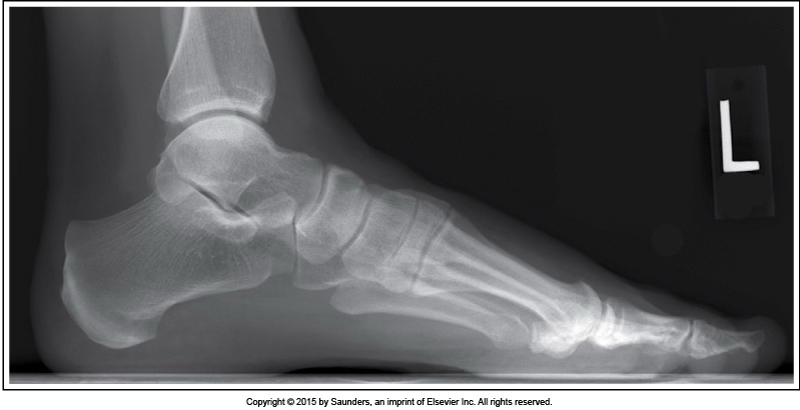

medialateral foot

accurate positioning

lateral foot

leg internally rotated

check fibula

pt has an average medial foot arch